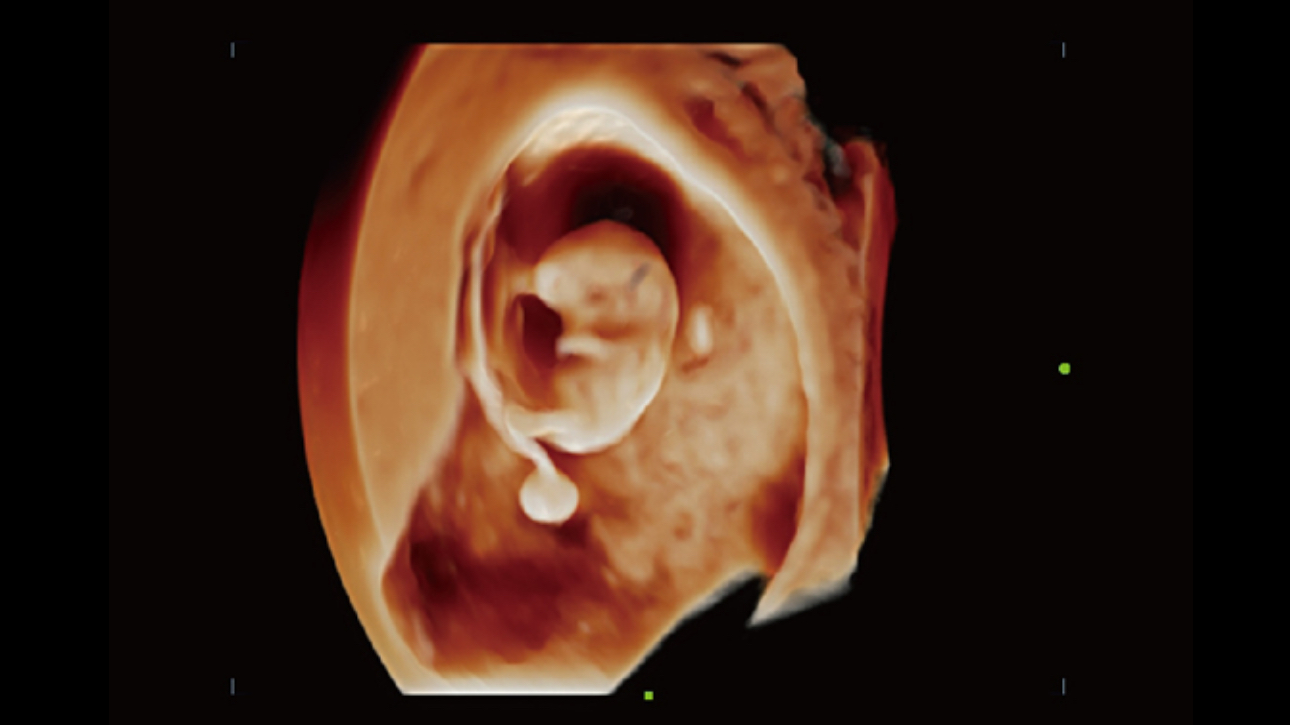

Smart Planes CNS provides a user-friendly tool that greatly improves scanning efficiency through increased accuracy coupled with automated operation. With a simple button click on a 3D fetal brain volume image, the standard CNS scanning planes (MSP, TCP, TTP and TVP) and a range of related anatomical measurements (BPD, HC, OFD, TCD, CM and LVW) are obtained immediately.

Acquiring an optimal view of the fetal face in 3DUS is cumbersome and time-consuming. In some cases, it is impossible to get rid of the occlusions such as cord, placenta, uterus, and extremities. The new Resona 6 with Zone Intelligence provides a fast and intelligent optimization for fetal face with simple one-touch operation. It can immediately remove occlusions in the volume data and eliminate unwanted noise information, and generate an optimal view of the fetal face with minimized effort.